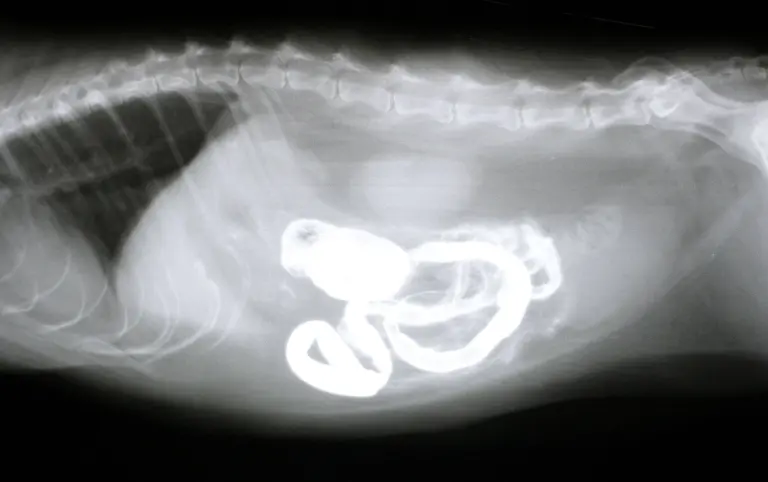

Socken, Kieselsteine, Außerirdische - Röntgenbilder von Mägen US-amerikanischer Haustiere zeigen die skurrilsten Gegenstände. Eine Zeitschrift zeichnet jedes Jahr die außergewöhnlichsten Aufnahmen aus.